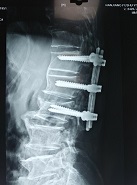

20161228日,在西安交大二附院王栋教授指导、协助下,吴晓鸿主治医师与李建栋副主任医师、王礼副主任医师及第五勇刚主治医师一起,顺利为该患者完成经后路全椎板减压、椎管内肿瘤切除、后路植骨内固定治疗。手术过程非常顺利,术后次日患者即感觉右下肢大腿及腹股沟疼痛症状消失。术后拍片复查见内固定稳定。减压、植骨效果良好。经过外二科护理团队的精心护理,患者现正在顺利恢复中。